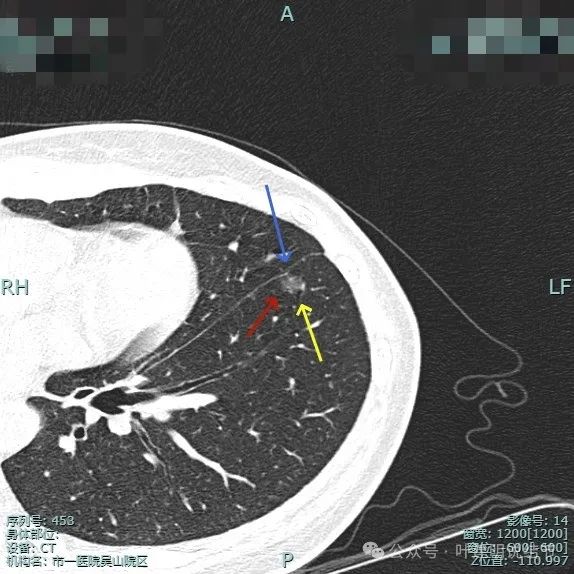

病灶边缘毛糙,微小血管进入明显。灶内密度略不均。

血管进入与穿行明显,而且在病灶内有发出血管分支,病灶表面不平,有毛刺征。

小血管进入明显,边缘有毛刺征,整体轮廓与边界清。

血管进入,灶内小空泡征,邻近细支气管有扩张,表面有细毛刺。

多处血管征,表面毛糙,轮廓清楚,有不太典型的血管弯征,灶内密度稍不均。